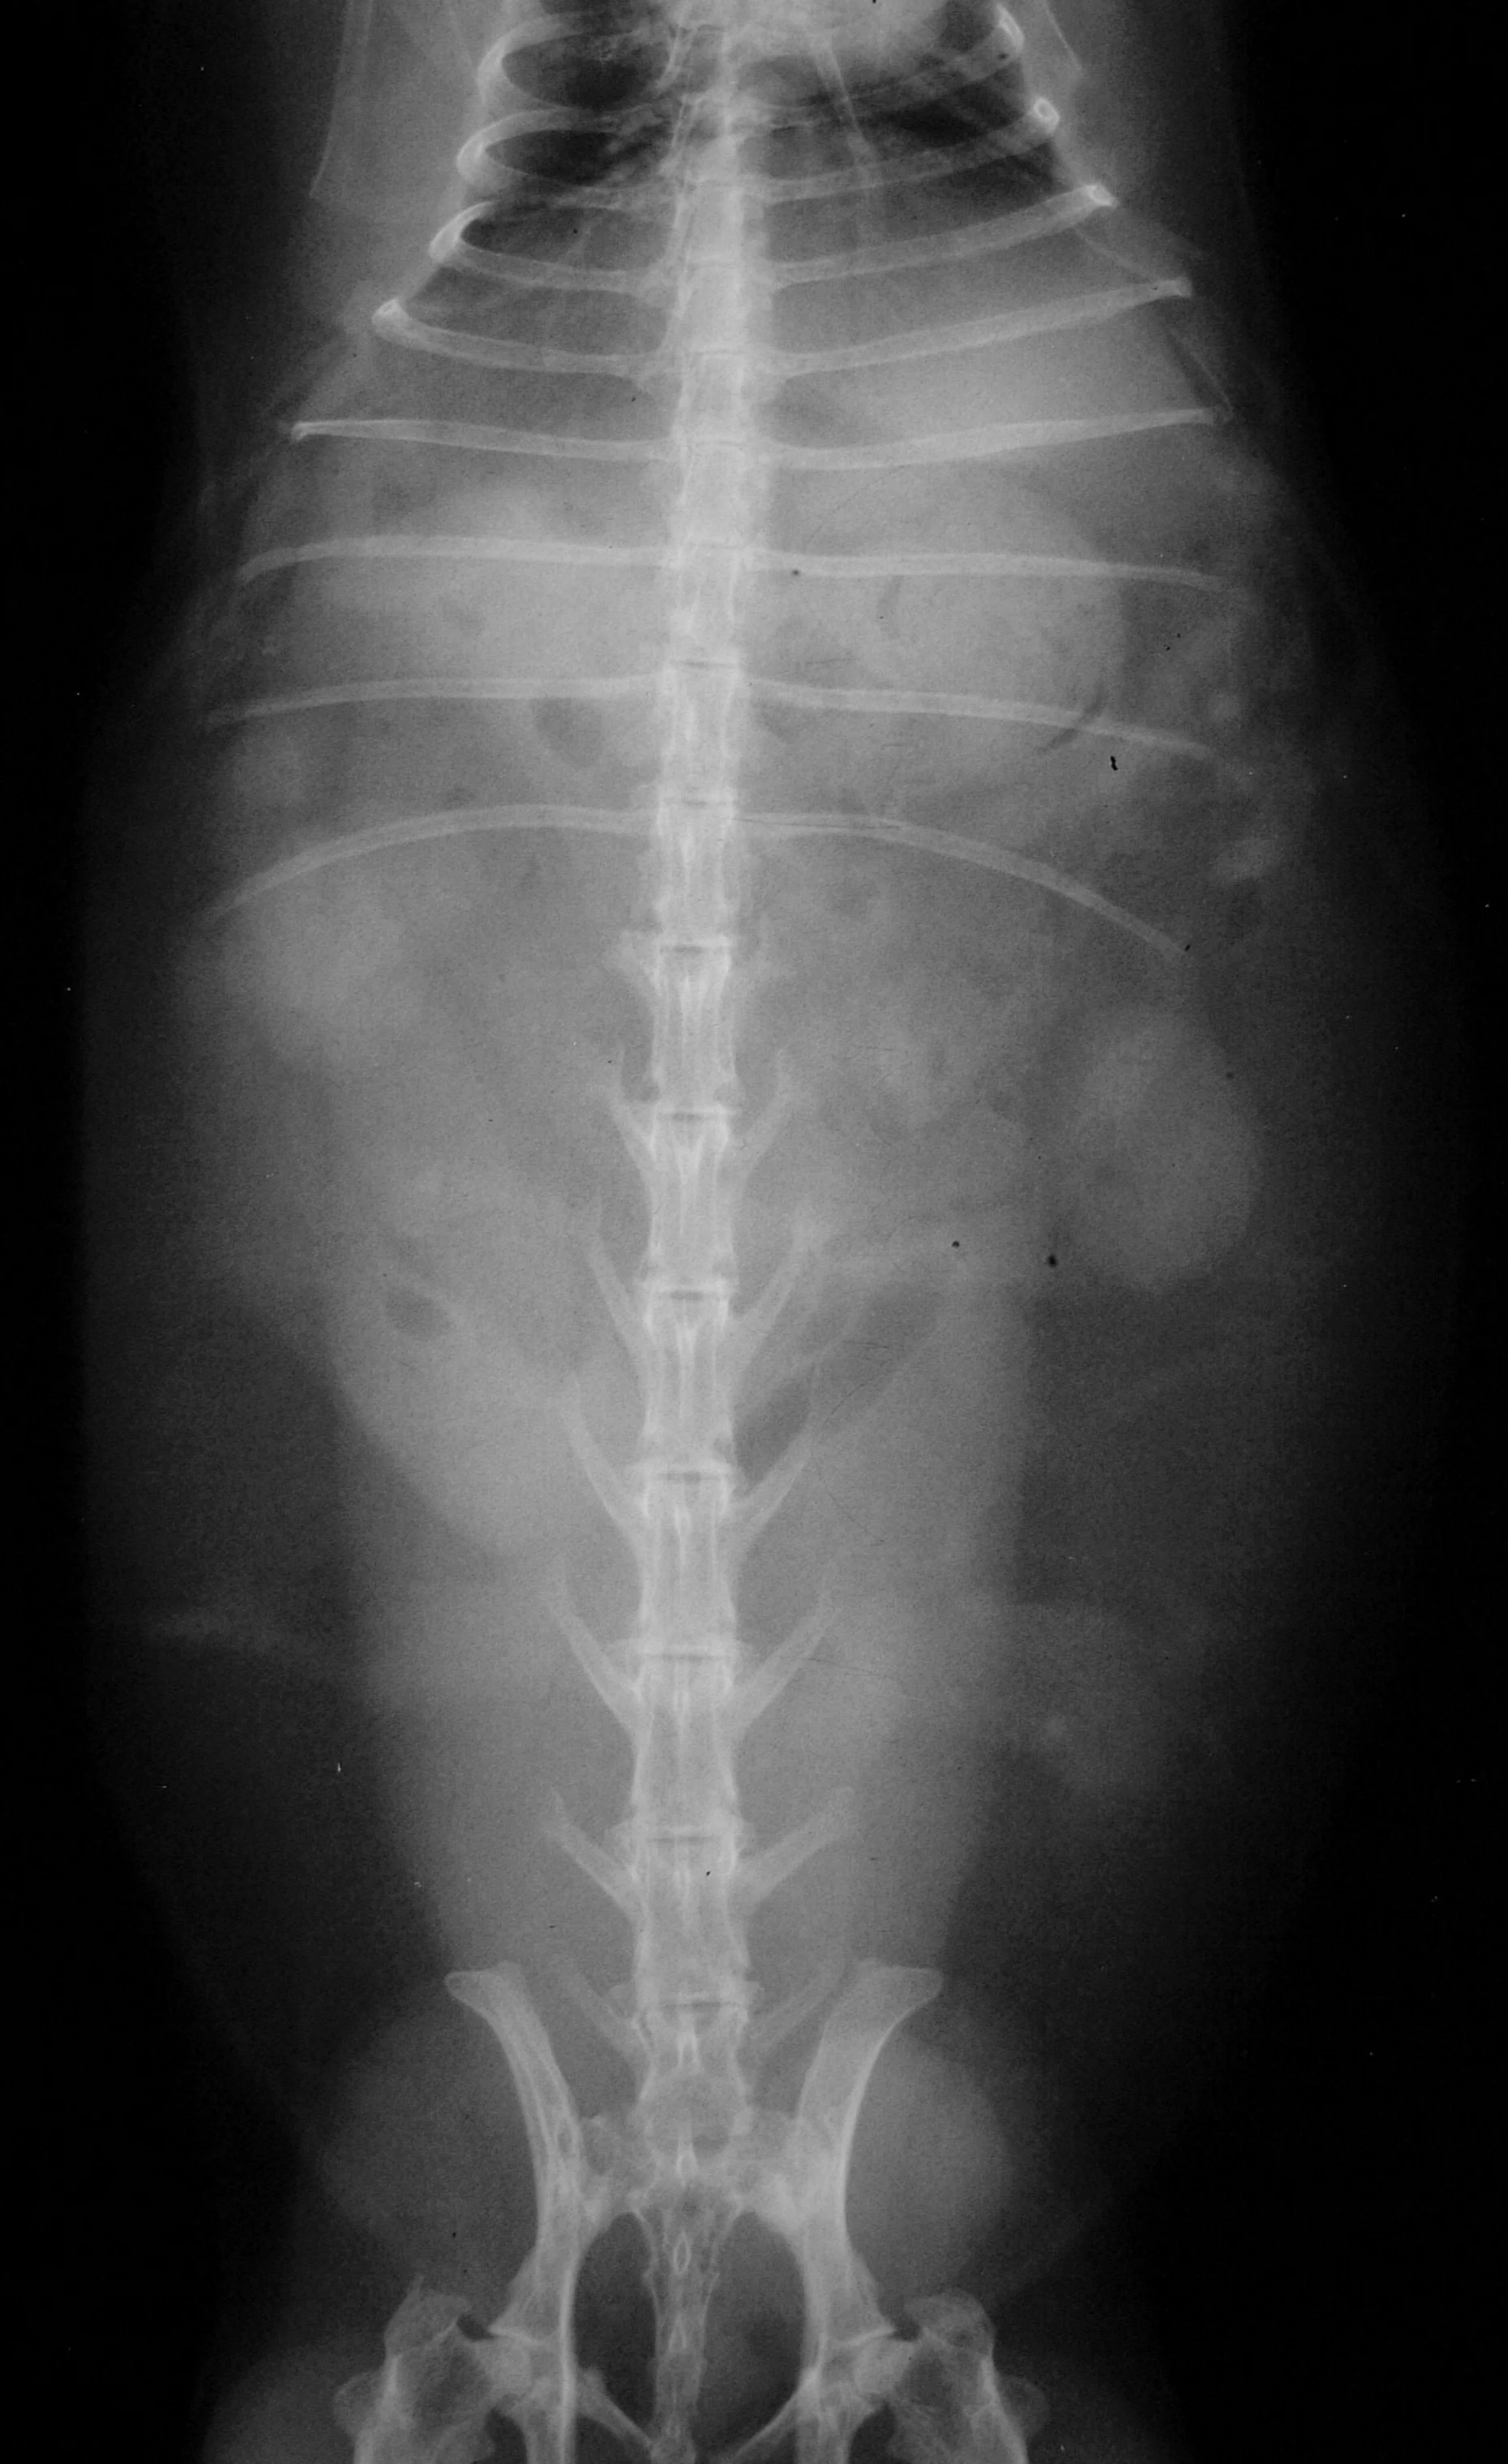

A CBC, biochemistry profile, and urinalysis were done. Results of the CBC were unremarkable except for a hematocrit of 28% with a regenerative response. All biochemistry values are within the normal range. Urine was obtained by free-catch. Urine specific gravity was 1.026, red blood cells were too-numerous-to-count, and a large amount of calcium sediment was noted. Radiographs (Figures 1 and 2) and a thorough dental examination were also indicated.

A soft-tissue opacity is apparent on the lateral radiograph (Figure 2) between the bladder and colon. Laparotomy was performed. What was removed is shown in Figure 3. Histopathology results revealed uterine adenocarcinoma. Uterine adenocarcinoma is a slow-growing tumor. Removed early in disease, the cancer is curable by ovariohysterectomy; no ancillary treatment is required. In this case the uterus was removed and there were no signs of metastasis. The rabbit was doing well when presented a year later for a checkup. Uterine adenocarcinoma is common in unspayed female rabbits. The only sign may be blood in the urine. In this case, the red urine did not alert the owners because the patient has had a history of porphyrin-colored urine and the red coloring from blood looked no different from porphyrin pigments.

The radiographs revealed no urinary tract calculi or "bladder sludge." Urinary tract calculi or sludge may only cause the rabbit to become lethargic and anorexic; signs of urinary disease may not be seen. Urinary tract disease is common in rabbits and may only present as nonspecific disease.